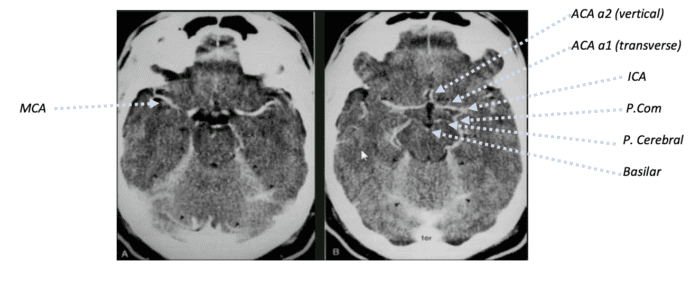

NeuroRadiology Booklet

Access here

Electronic booklet aimed for medical students and neurology residents, covers the basics of neuroradiology from the scratch.